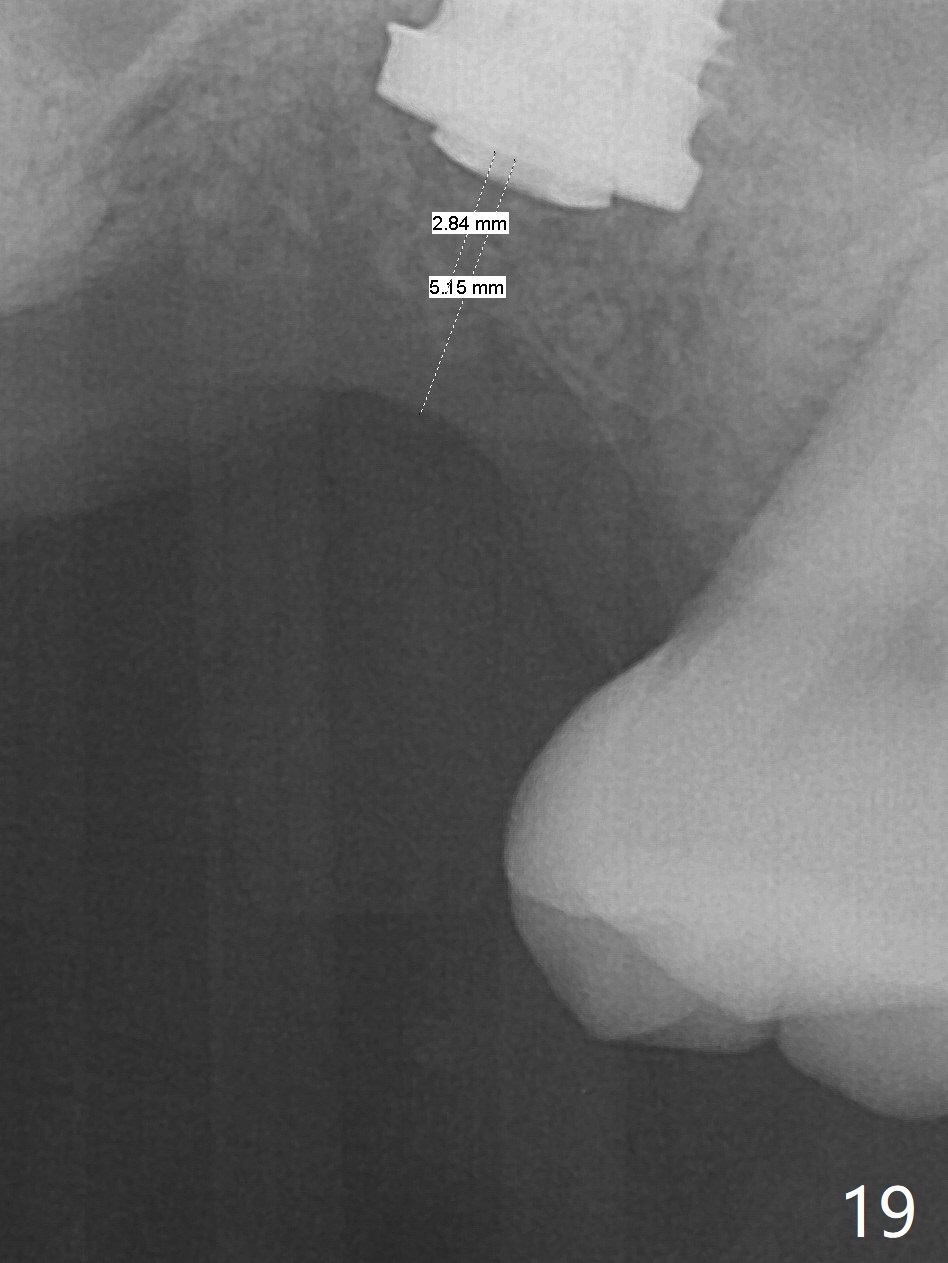

Poor visibility for immediate implant in the molar region is another contributing factor for the dislodgement.  The patient returns for follow up 15 days (Fig.15) and 1 month (Fig.16) postop.  Bone graft seems to be stable around the implant.  The socket heals 4 months postop (Fig.20).  The implant seems to have been osteointegrated (Fig.17,18).  It will be backed up for ~ 3 mm to improve implant/crown ratio (Fig.19, as compared to Fig.14).  If it cannot be done, take impression immediately and make a subgingival provisional before suturing.